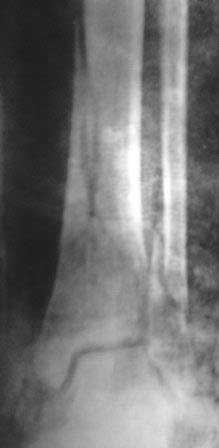

[Ortho] Вялоконсолидирующаяся перелом дистального метадиафиза костей левой голени

Пациентка 32 года, травму получила в результате ДТП, лечилась в гор.б-це №? Москвы с 19.07.по04.08.11г скелетным вытяжением, после наложена гипсовая повязка,(р-снимок 1,2.) после спадения отека гипс переведена в циркулярную, (видимо на другой вид лечения не хватило средств), гипс снят 19.11.11г(снимок-3)

.Жалобы на боли при ходьбе через несколько шагов, увеличение отека в голени и г/стопном суставе, боли ноющего и неприятного характера, хромота, при осмотре отечность голени в с-н/з и г/с суставе, при пальпации умеренная болезненность в н/з голени, подошвенное сгибание в г/с суставе ограничена и болезненна. Работа связана с ходьбой, просить помочь чтобы не потерять работу. Пока в голове только КДО аппаратом Илизарова, уважаемые коллеги  помогите советом! Доступно БИОС, пластины DCP. и прилагается последние р-снимки.